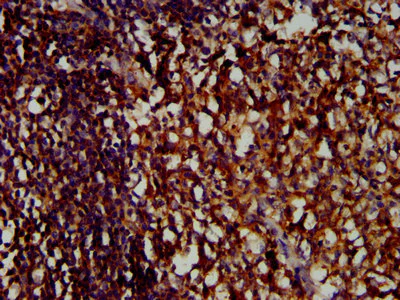

Immunohistochemistry (Formalin/PFA-fixed paraffin-embedded sections) - Anti-LILRB1 antibody (AB237625)

Paraffin-embedded human tonsil tissue stained for LILRB1 with ab237625 at a 1/400 dilution in immunohistochemical analysis.

After dewaxing and hydration, antigen retrieval was mediated by high pressure in a citrate buffer (pH 6.0). Section was blocked with 10% normal goat serum 30 minutes at RT. Then primary antibody (1% BSA) was incubated at 4°C overnight. The primary is detected by a biotinylated secondary antibody and visualized using an HRP conjugated SP system.